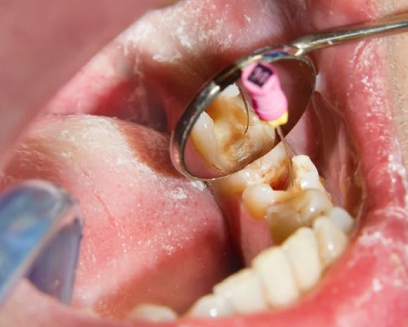

Root canal treatment at Nebras Medical Center in Ras Al Khaimah

is needed when the tooth’s pulp becomes infected or damaged.

This can occur due to severe decay, deep cavities, repeated dental

procedures on the tooth, or trauma.

Symptoms indicating the need for a root canal include persistent tooth pain, prolonged sensitivity to heat or cold, gum swelling, and discoloration of the tooth. The procedure helps relieve pain, eliminate infection, and preserve the tooth, preventing the need for extraction.

How long does a

Root Canal take?

A root canal procedure at Nebras Medical Center in Ras Al

Khaimah typically takes about 60 to 90 minutes. The duration can

vary based on the complexity of the case, the number of roots in

the tooth, and whether additional treatments, like a crown, are

needed.

Most root canals can be completed in one visit, but in some cases, a follow-up appointment may be required for final restoration.